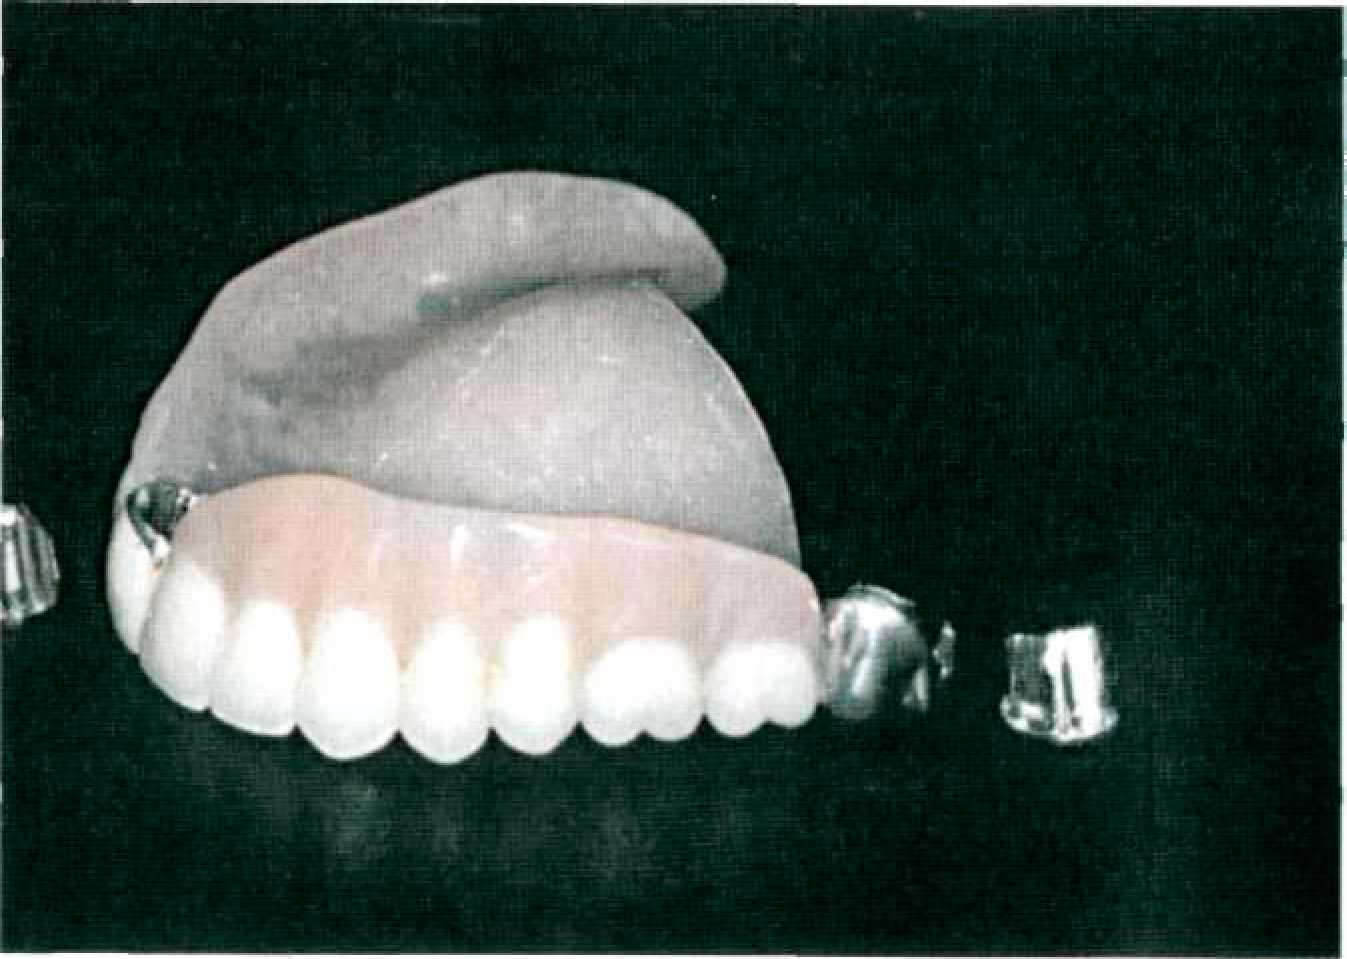

Этап 12. В клинике проводится припасовка каркаса съемного протеза и вторичных коронок. Проверка конструкции проводится при неактивированных фрикционных штифтах. Если вторичная телескопическая коронка не обладает достаточной силой сцепления, это может означать, что она опирается на торец внутренней телескопической коронки. В этом случае необходимо с помощью грубого резинового диска отполировать торец первичной коронки так, чтобы боковые прилегающие поверхности контактировали друг с другом. Аналогичная проблема возникает, если вторичная телескопическая коронка упирается в первичную в пришеечной зоне до того, как соприкоснутся их боковые поверхности. В этом случае следует пришлифовывать эту ступеньку в наружной телескопической коронке. На этом этапе проводят выбор цвета искусственных зубов. Этап 13. В лаборатории проводят облицовку вторичных телескопических коронок, постановку зубов и замену воскового базиса на пластмассу по общепринятой технологии (рис. 143).